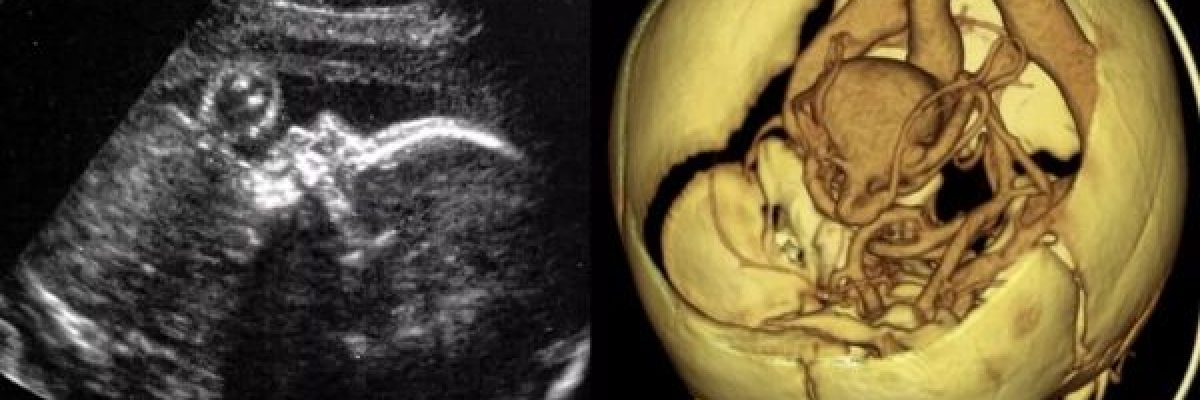

وباستخدام الموجات فوق الصوتية، تمكن الاطباء من علاج التشوه الذي يسبب تدفقا للدم بسرعة كبيرة عبر جزء من الدماغ، وهي اول حالة مماثلة يتم علاجها بهذه الطريقة، وفق ما نقلت قناة الحرة.

واجرى اورباخ وزملاؤه العملية على جنين في الاسبوع 34 من الحمل، واستخدموا الموجات فوق الصوتية لارشادهم اثناء العملية، وولد الطفل بعد يومين لان العملية تؤدي الى تمزق الاغشية في الرحم، فيولد قبل الاوان.